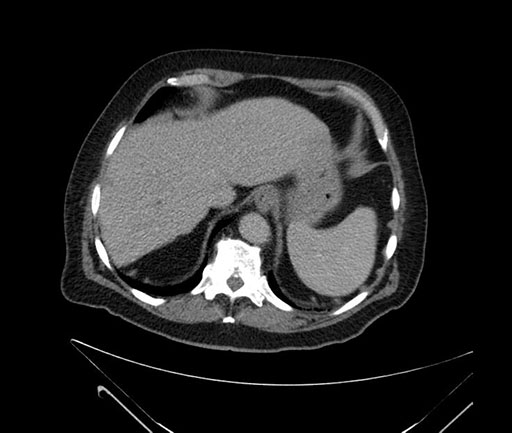

Imaging Analysis

Look through the patient's CT scan to identify any areas of concern for the necessary procedure.

Based on your CT findings, which issue(s) would give reason for "planned slowing down moment(s)" in this case?

Considering a standard Whipple procedure, what step(s) of the operation would you do differently in this case?